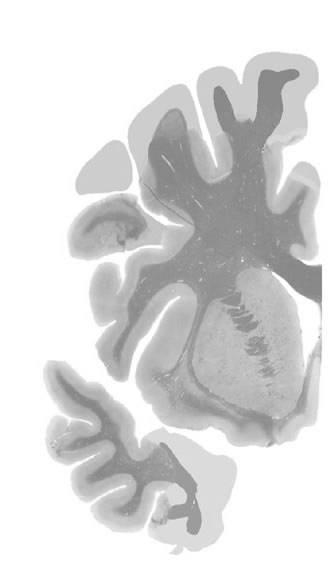

Hi-Resolution Sections · Cells (Nissl Staining) · Virtual Microscopy

Frontal sections (Nissl) from the Atlas Brain:

Slice ID:

r2-0352

Plate NR:

12-13

Position:

-13,7 mm